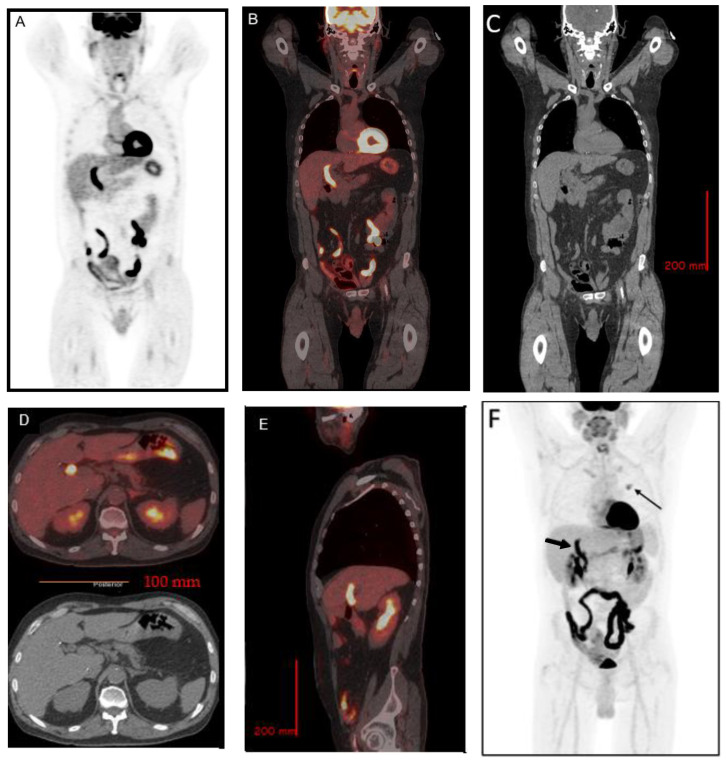

Due to incidental CT findings of a left upper lobe pulmonary nodule, an [18F] FDG positron emission tomography (PET) was performed approximately one month post-ERCP. In addition to a moderately hypermetabolic left upper lobe pulmonary nodule, which was later proven to be a metastasis from colon cancer, there were incidental findings of increased uptake in the CBD, with a SUVmax of 13.3, suspicious for cholangitis (Figure 2). A follow-up magnetic resonance cholangiopancreatography (MRCP) was performed 9 days after the [18F] FDG PET showed no evidence of cholangitis, pancreatitis, or choledocholithiasis (Figure 3).